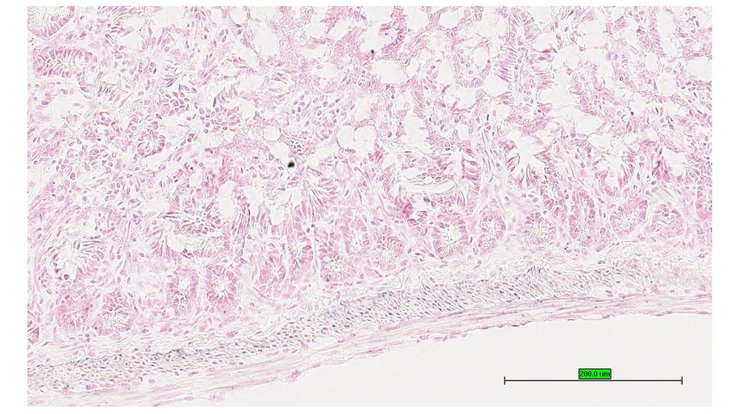

TS28: jejunum Present UC Davis_1889717

TS28: jejunum Present UC Davis_1889718